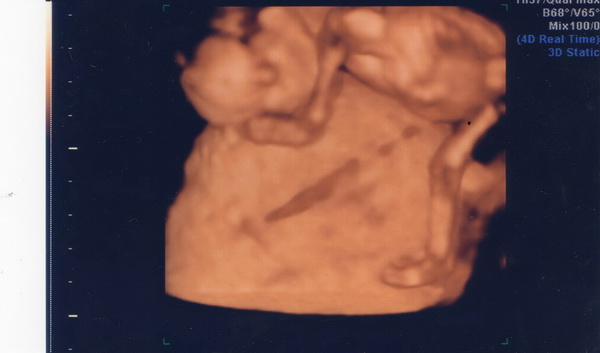

A méhlepényen hasal